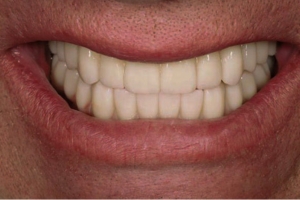

✅ приємний пріродний виглядмзубів, але при різних протоколах є питання “рожевої естетики”.

✅ швидкий та довготривалий результат.